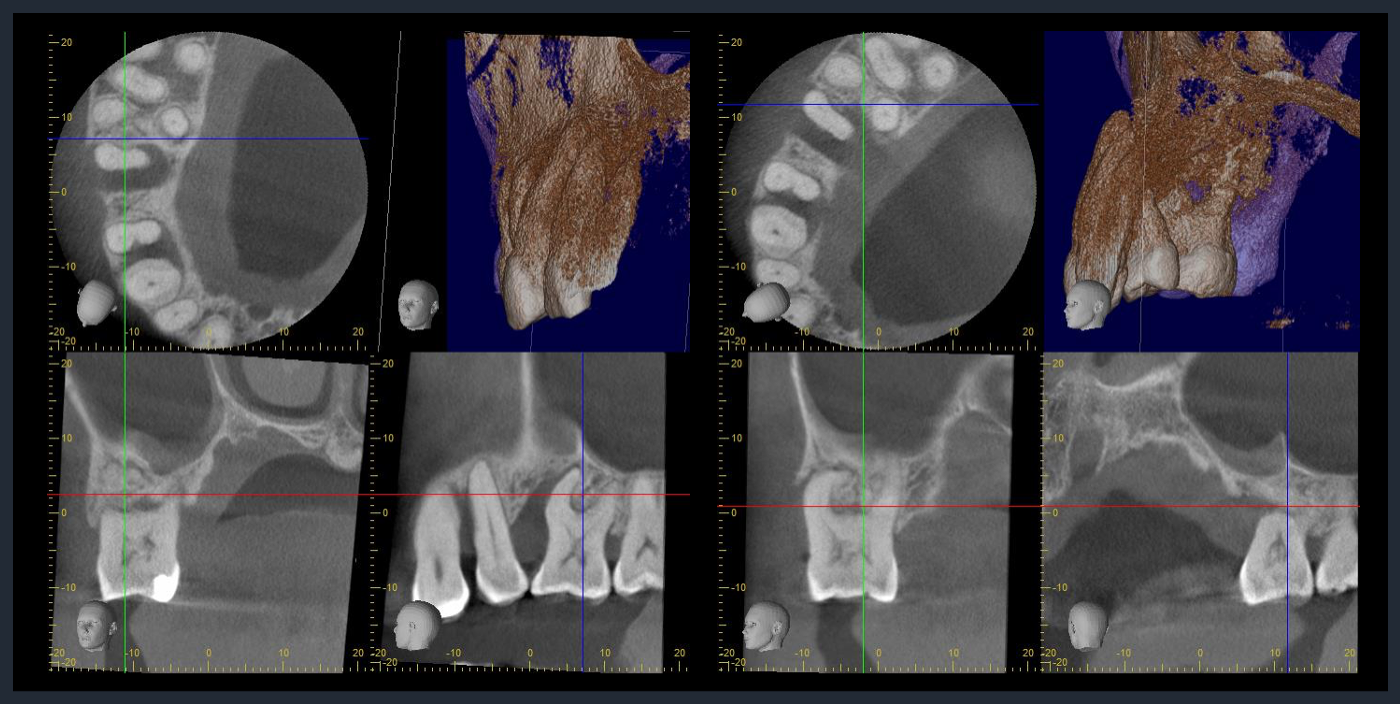

CTでの術前診査2